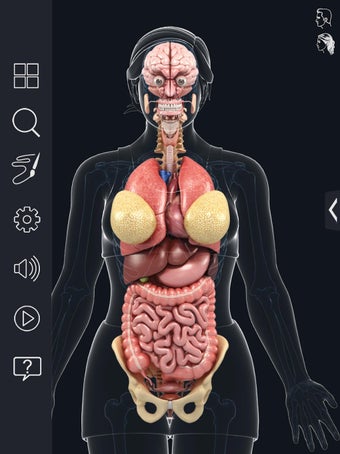

Met deze applicatie kun je 360° draaien rond een zeer realistisch 3D-model van het menselijk lichaam. Je kunt in- en uitzoomen op elk deel om er beter naar te kijken.

De camera kan worden verplaatst om een ander beeld van elk deel te krijgen.

Je kunt alle informatie over de organen krijgen, inclusief hun locatie, hun functie en hoe ze eruitzien.